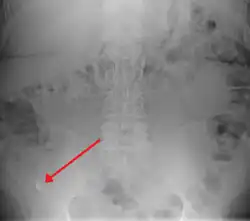

X-ray

Appendicolith as seen on plain X-ray.

In general, plain abdominal radiography (PAR) is not useful in making the diagnosis of appendicitis and should not be routinely obtained from a person being evaluated for appendicitis.[70][71] Plain abdominal films may be useful for the detection of ureteral calculi, small bowel obstruction, or perforated ulcer, but these conditions are rarely confused with appendicitis.[72] An opaque fecalith can be identified in the right lower quadrant in fewer than 5% of people being evaluated for appendicitis.[48] A barium enema has proven to be a poor diagnostic tool for appendicitis. While failure of the appendix to fill during a barium enema has been associated with appendicitis, up to 20% of normal appendices do not fill.[72]